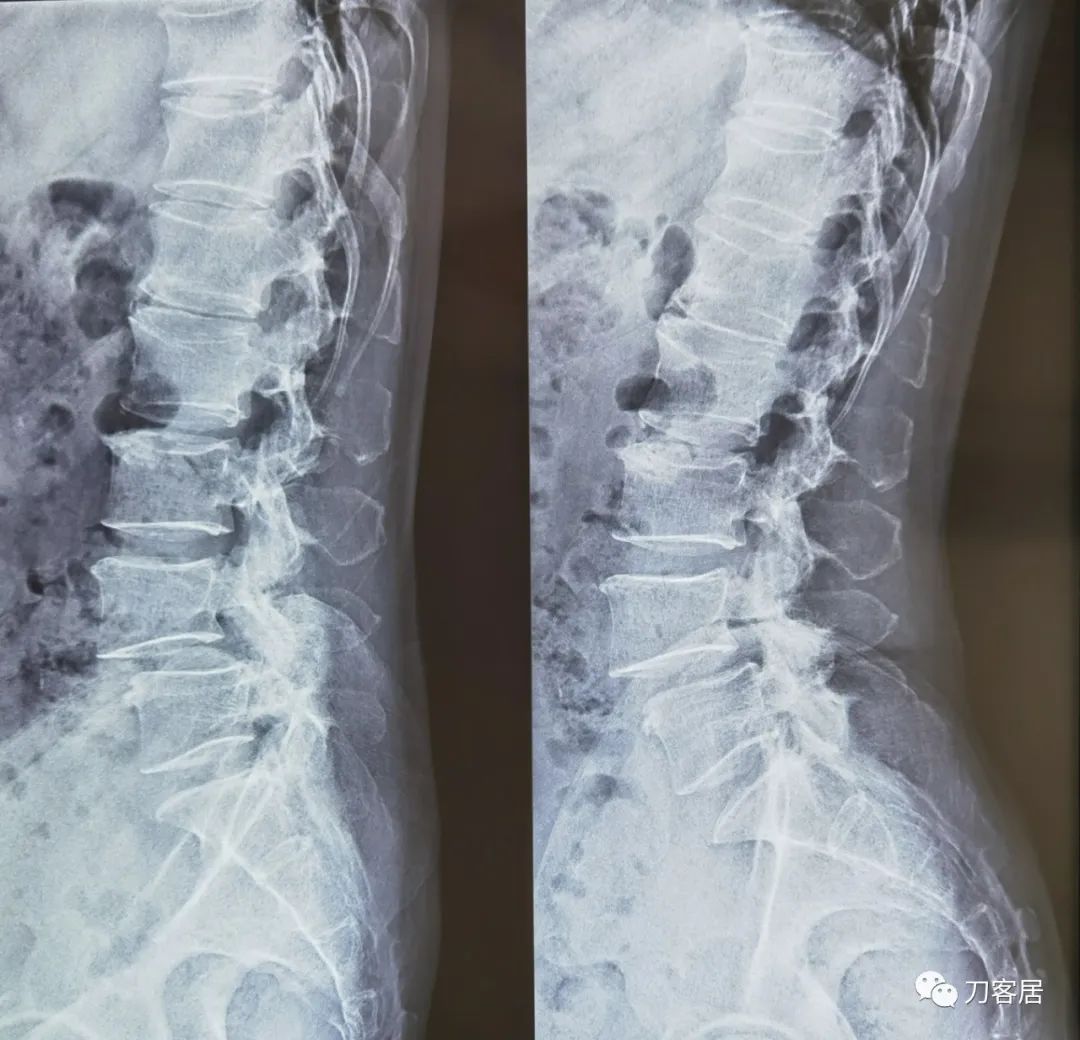

给予腰椎6位片检查,以了解腰椎的稳定性及是否存在峡部裂,腰椎6位片提示右侧腰4峡部裂,腰4椎体稳定性差。

图2. 20220615腰椎双斜位X线片

图3. 20220615腰椎过伸过屈位X线片